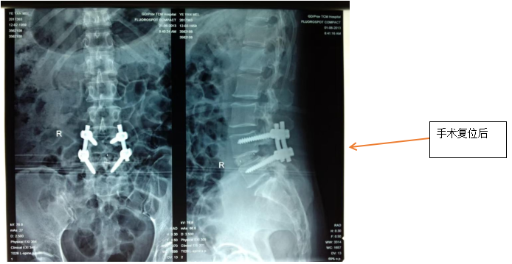

經皮微創置釘脊柱融合術手術與非融合手術

融合術:適用于腰椎管狹窄、腰椎滑脫等需穩定脊柱的病例;

非融合術:主要用于脊柱骨折等短期固定需求。

兩種術式均通過經皮置入椎弓根螺釘,避免傳統開放手術對腰背肌肉的大范圍剝離,具有出血少、疼痛輕、康復快等優勢。

腰椎滑脫手術復位固定